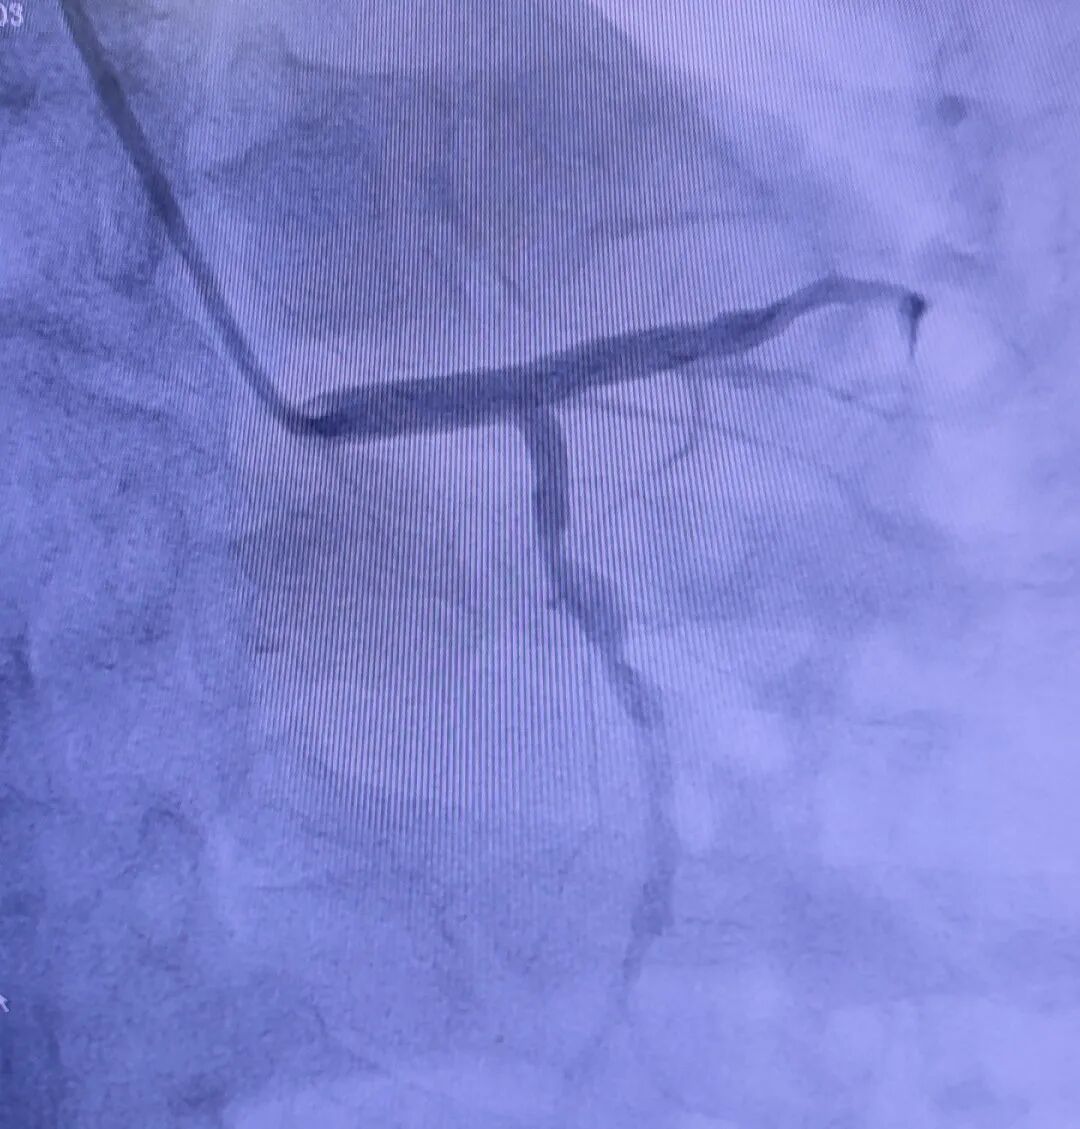

✦ ✦ ✦ 葫芦岛市第二人民医院心脏血管外科 汇聚北京301/阜外/安贞专家团队 国家级顶尖技术全程护航 原解放军301医院 李寒教授、汤楚中教授领衔 联合北京阜外、北京安贞顶尖专家团队 从检查、手术到康复 全程北京专家护航! 年过六旬的赵大爷(化名)入院前一周突发高烧,体温飙升至39.7℃,以为只是普通感冒,但吃药后却未见缓解。为求精准治疗,家属将其送至我院。 检查结果让所有人倒吸一口凉气!经食道超声发现,赵大爷心脏二尖瓣上长出一个约13x10mm的赘生物,血培养证实为“金黄色葡萄球菌”引发的感染性心内膜炎。这个赘生物就像一颗“不定时炸弹”,随时可能脱落流入大脑或重要脏器,引发致命栓塞。 患者明确满足手术指征,但治疗之路布满荆棘。此时赵大爷仍反复高烧,处于感染急性期,必须先控制感染才能手术。 心脏中心副主任、心脏血管外科著名专家李寒教授领衔团队凭借在解放军总医院(301医院)多年积累的急危重症处理经验,精准施策,经过一个多月的对症治疗,赵大爷体温趋于稳定,手术时机终于成熟! 术前造影 术前,李寒教授团队进行了极其周密的评估,并安排了冠脉造影检查。造影显示:患者回旋支粗大,近段弥漫性狭窄,近钝缘分支叉狭窄约70%~80%,右冠中远段100%闭塞。这意味着,患者不仅需要解决二尖瓣赘生物和感染问题,还需同期实施冠状动脉搭桥术,手术难度和风险大幅提升。 “患者把命交到二院,我们必须拿出最优解。”李寒教授团队迎难而上,制定周密手术方案。在体外循环技术支持下,团队为赵大爷同期实施“二尖瓣生物瓣置换术”+“主动脉-冠状动脉搭桥术”。术中既要精准切除感染病灶、置换新瓣膜,又要在跳停的心脏上,用比头发丝还细的缝线重新搭建“生命通道”,恢复心肌供血。整个手术过程有条不紊,精准高效。当心脏重新恢复有力的跳动时,意味着这台高难度手术的成功。 术后,在心脏血管外科医护团队的精心照料下,赵大爷的恢复情况远超预期。术后仅3天,他就能下床行走,精神状态和饮食情况也一天比一天好,脸上终于露出了久违的笑容。 此次高难度手术的成功,再次展现了我院心脏血管外科的硬核实力。作为葫芦岛首家心脏血管外科,科室由原解放军总医院(301)心血管外科专家李寒教授、汤楚中教授领衔,深度联合北京安贞医院、阜外医院顶级专家团队,构建 “北京技术、滨城落地” 的创新模式。滨城百姓再也不用奔波劳顿赴外地求医,在家门口就能享受到国家级的诊疗服务。科室不仅填补了本地区心脏血管外科的空白,更以国内先进水平的手术成功率和术后生存质量,为无数重症心脏病患者托起了“心”的希望。 葫芦岛市第二人民医院心脏血管外科作为葫芦岛市首家心脏外科专科及医院重点发展学科,打造集危急重症抢救、复杂手术攻坚、终身健康管理于一体的区域性心脏诊疗高地。 由原解放军总医院(301)心血管外科专家李寒教授、汤楚中教授领衔,深度联合北京安贞医院、北京阜外医院顶级专家团队,构建“北京技术、滨城落地”的创新模式,是辽西首个实现“北京心脏技术本地化”的专业团队,为复杂心血管疾病患者提供国家级诊疗服务。 科室配有CRRT、呼吸机、除颤仪、血气分析仪、主动脉球囊反搏泵等先进设备。全面开展冠状动脉搭桥术、复杂瓣膜置换术(二尖瓣、三尖瓣、主动脉瓣)、瓣膜成形术、主动脉夹层手术、房间隔修补术、室间隔修补术、心包疾病(缩窄性心包炎、心包肿瘤)等复杂心脏血管外科手术,年开展心脏外科手术量及复杂病例占比持续领跑区域医疗行业。 科室率先推行围术期(从术前准备到术后康复)全程北京专家管理模式,保障患者整体健康和长期预后,极大提高了手术成功率,改善了患者生活质量,为众多心脏病患者带来生命的希望和健康的未来。 心脏血管外科年均手术300余例,复杂手术占比超40%,术后生存率达国内领先水平,填补辽西地区多项技术空白,持续引领区域心血管疾病诊疗技术革新,让患者在家门口享受国家标准心脏诊疗服务。 李寒 主任医师 教授 ·葫芦岛市第二人民医院心脏中心副主任、心脏血管外科著名专家 ·原解放军总医院(301)第六医学中心心外科主任、北京中医药大学东直门医院心外科主任 ·北京医学会心血管外科分会委员 ·全军胸心血管外科学会青年委员 ·国家药品食品监督管理局医疗器械评审专家 ·北京转化医学会心外科分会常委 ·中国民族卫生医药学会心脏分会委员 专业特色:从事心脏大血管外科工作30余年,长期致力于复杂心脏大血管外科治疗工作,参与偏远地区先心病患儿救治数量4千余例,并在国内开展了多项领先及高难技术,如冠状动脉旁路移植术中干细胞移植,干细胞移植治疗右室型心肌病、先心病合并重度肺动脉高压的诊断性治疗等。擅长冠心病、瓣膜性心脏病、先天性心脏病、心脏肿瘤以及大血管病等手术治疗。开展多项新技术新业务,包括:冠脉搭桥、瓣膜修复、置换、先心病矫治、主动脉夹层、动脉瘤外科手术、心包炎、心脏肿瘤等心脏外科高难手术,外科手术中射频消融治疗心房颤动等,均在国内属于先进水平。 李寒主任已正式入驻抖音,扫码关注或搜索“心脏外科李寒主任”,了解更多心脏知识。